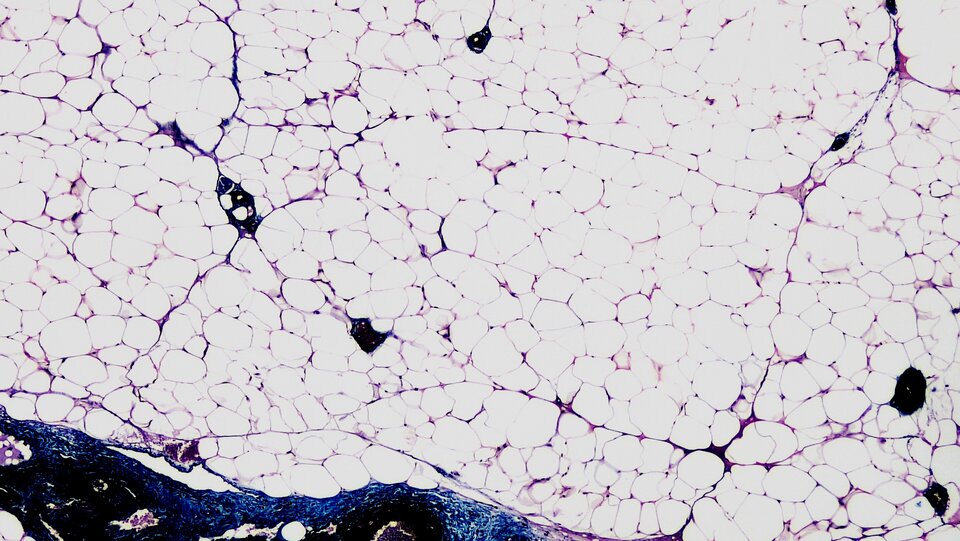

Tłuszcze właściwe, zwane triglicerydami (trójglicerydami, triacyloglicerole) to estry glicerolu i połączonych z nim wiązaniem estrowym cząsteczek wyższych kwasów tłuszczowychkwasów tłuszczowych. Tłuszcze właściwe w organizmach zwierząt magazynowane są w postaci tkanki tłuszczowej żółtejtkanki tłuszczowej żółtej i tkanki tłuszczowej brunatnejtkanki tłuszczowej brunatnej, zlokalizowanych głównie pod skórą oraz wokół narządów wewnętrznych.